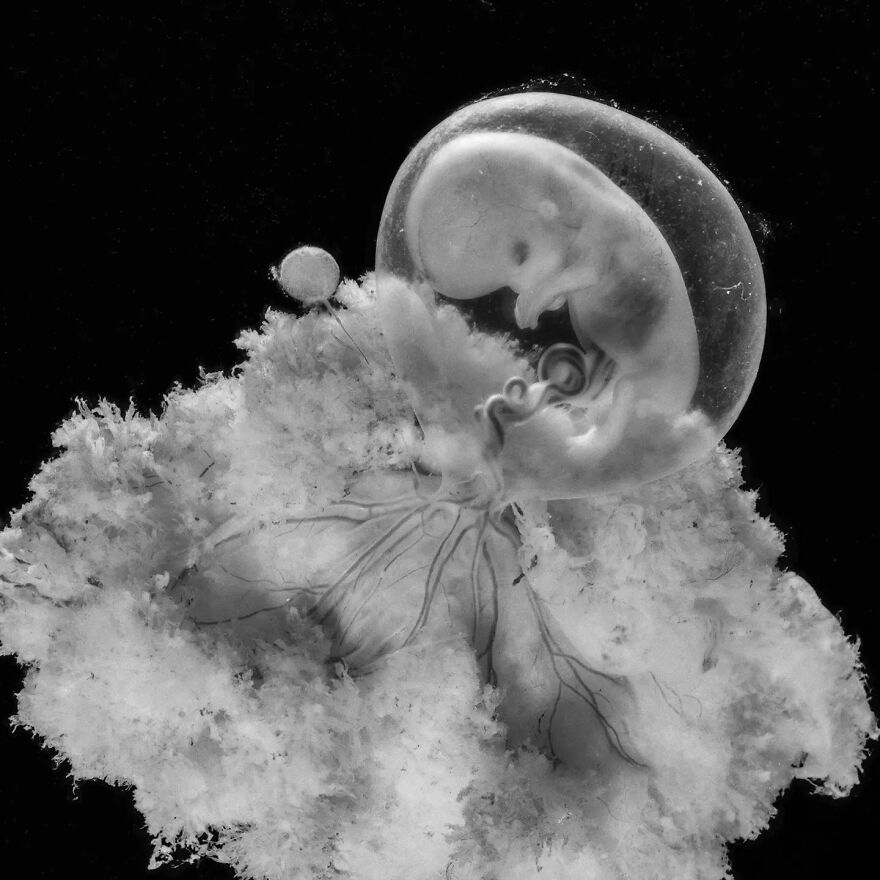

Зарождение жизни: Фотографии Леннарта Нильсона